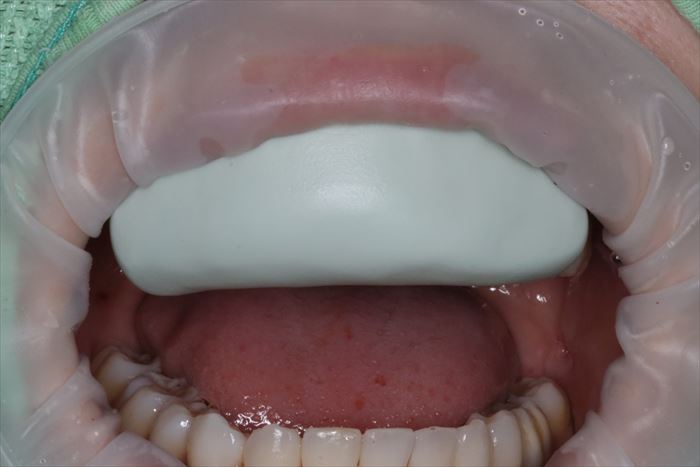

前歯のインプラント治療の際には仮歯が必要となりますので、現状の形をシリコンで型取りして

レジンを流しこみ仮歯を製作するための型を準備をしておきます。

さらに、レジンで製作した仮歯を元の位置に戻すためのシリコンジグを採っておきます。

事前の準備が術中のストレスを減らしますので、不安要素を徹底的にクリアしておくことを私は好んでいます。

前日までに準備しておくべき内容と、このケースの様に当日の状態に即して準備する方が良い内容があります。